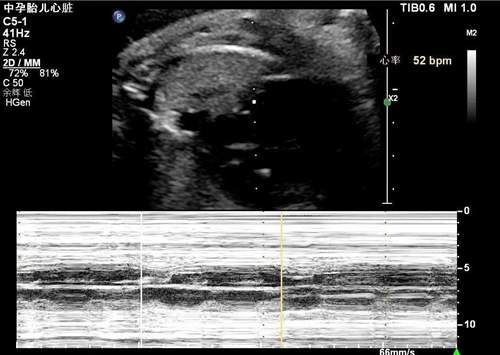

近日, 28歲的高女士(化名)在懷孕32周產(chǎn)檢時(shí)發(fā)現(xiàn)胎兒心率僅有70次/分,當(dāng)?shù)蒯t(yī)院考慮為“胎兒窘迫”,被緊急轉(zhuǎn)往青島婦女兒童醫(yī)院胎兒醫(yī)學(xué)中心就診。

經(jīng)過接診醫(yī)生的仔細(xì)排查,發(fā)現(xiàn)胎兒心跳緩慢的原因不是 “胎兒窘迫”,而是一種緩慢型的心律失?!渴覀鲗?dǎo)阻滯。

“此類型心律失常很少在妊娠晚期發(fā)生,并且孕婦本人也沒有導(dǎo)致胎兒心律失常的常見高危因素,比如一些自身免疫性疾病”,胎兒醫(yī)學(xué)中心副主任張?zhí)@介紹道?!靶碾妶D提示孕婦本人右束支傳導(dǎo)阻滯,雖然在成年人中比較常見,但是結(jié)合胎兒心律失常的癥狀,我們認(rèn)為并非巧合”。